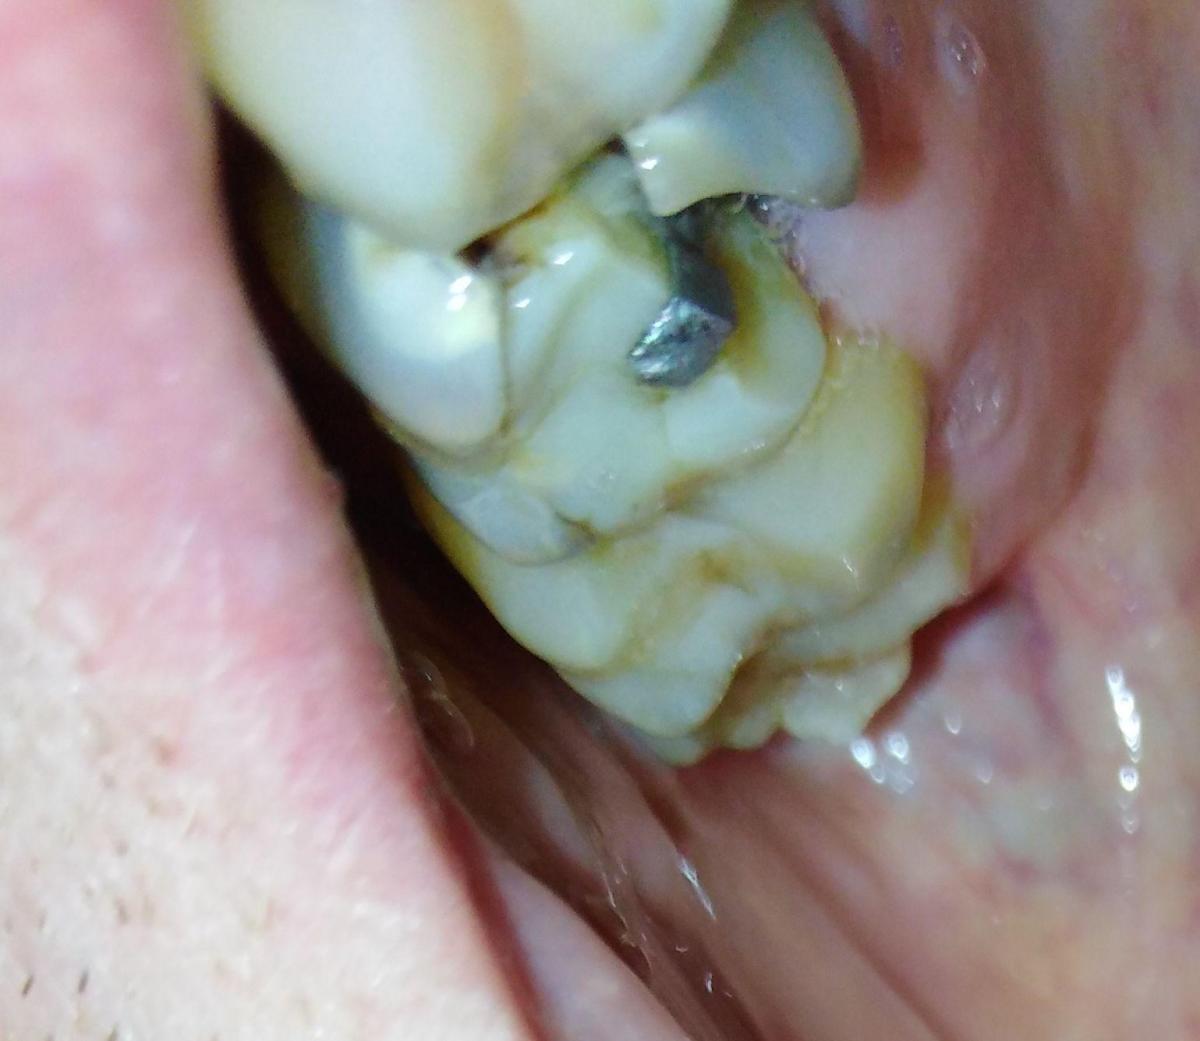

Интересовала в частности развалившаяся 6-ка сверху.

уже давно леченная -перелеченная.

По поводу 6 ки я еще готов удалить так как там похоже невозможно что-то сделать но 4-ка с 5-кой свиду не такие плохие. возможно их перелечить ?

6-ку я так понимаю все-равно лучше удалить ? у меня такая же на другой стороне там тоже огромная пломба со штифтом

вот уже лет 10 и пока стоит. Если вычистить и опять сделать пломбу ( понятно что коронке не на чем держаться.)